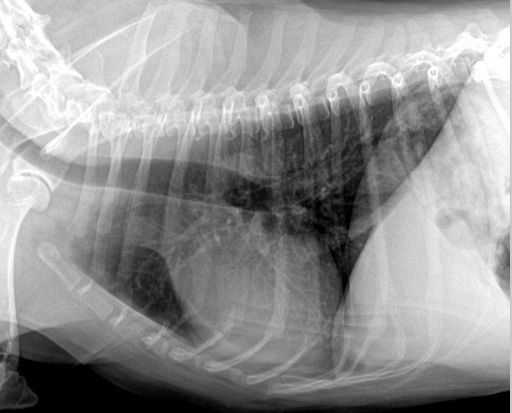

| RL (Right Lateral) | LL (Left Lateral) |

![]() | ![]() |

| ๋ ovalํจ. | ์ฌ์ฅ์ด ๋ ๋ฅ๊ธ๊ฒ ๋ณด์(round). |

| ๋ํ ์ผํ ์ฌ์ฅ ๊ด์ฐฐ์ ์ข์. | ํํ๊ด ์ดฌ์์ ์ข์. |